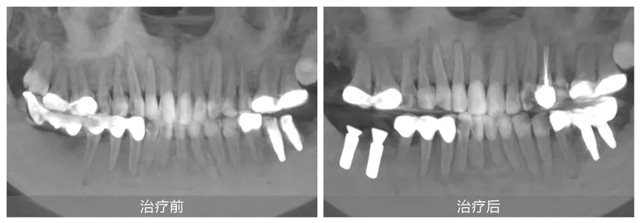

她自小牙齒不好,早年正牙過程中不幸遭遇正畸片切不當(dāng)導(dǎo)致下頜右側(cè)兩顆磨牙嚴(yán)重受損,之后未經(jīng)正規(guī)處理直接拔牙,造成重要磨牙缺失,嚴(yán)重影響咀嚼功能。隨后原治療機構(gòu)采用傾斜智齒制作了不良烤瓷長橋修復(fù),導(dǎo)致前磨牙牙髓壞死造成根尖炎。雪上加霜的是,五年前又被某口腔機構(gòu)蹩腳醫(yī)生把上頜兩側(cè)磨牙做了不必要的牙冠,之后下頜左側(cè)兩顆磨牙也因種植體位置不正導(dǎo)致牙冠頻繁脫落,種植體也有折斷風(fēng)險。

果然,徐會醫(yī)生不負所托輕松完成了劉女士下頜左側(cè)的牙冠修復(fù)。并對其他牙齒問題提出了一套綜合治療方案:先拆除不良修復(fù)體,拔除下頜右側(cè)的傾斜智齒,然后在缺牙處植入兩顆種植牙,并對前磨牙實施根管治療。這一方案更加微創(chuàng),也更加經(jīng)濟和高效。